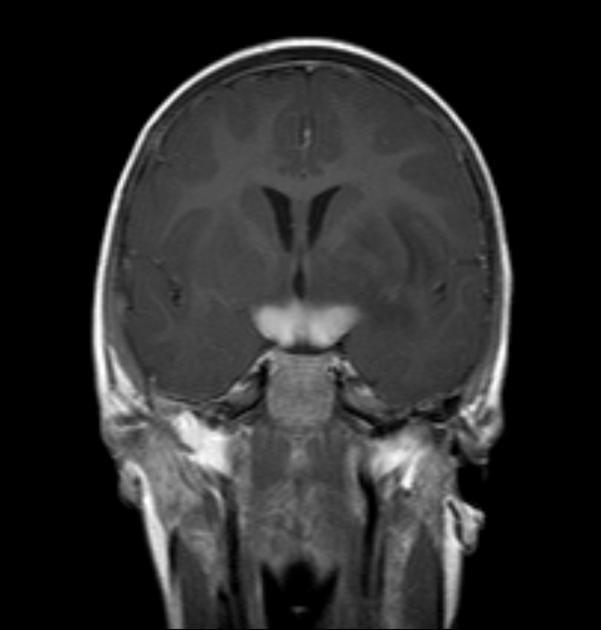

图 2 MRI 检查,冠状位 T1WI 增强序列显示视神经交叉及双侧视神经走行区肿胀,呈明显强化改变

图 3 MRI 检查冠状位 T2WI 序列和 T1WI 强化序列显示,双侧视神经部分节段肿胀呈长 T2 信号,强化呈明显强化改变